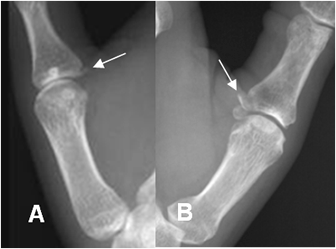

Fig 60. Fractura del esquiador.

A y B: Rx oblicuas. Fracturas por avulsión en diferente grado, sobre la base de la falange proximal del 1º dedo, por lesión del esquiador.